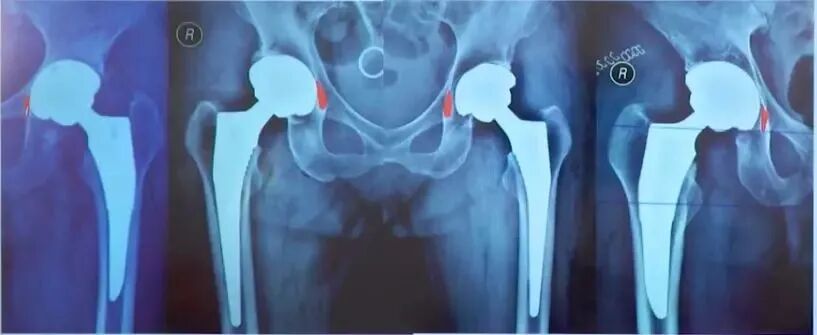

四、髋关节置换术后评估

术后评估内容:

①肢体长度:真实长度(髂前上棘到内踝长度);

②影像学长度(耻骨下沿连线通过双侧股骨同一高度)

③髋臼角度:外展角在35°-45°之间前倾角在15°-20°之间;

④髋臼位置:恰好贴近泪滴外绿的外侧,日杯缘应位于髋臼内外侧壁之间;

⑤假体触面:假体骨界面;假体骨水泥界面;骨水泥骨界面;

⑥股骨假体:颈干角、前倾角、柄-髓腔。

肢体长度:

真实长度(髂前上棘到内踝长度)测量即可;

影像学长度(耻骨下沿连线通过双侧股骨同一高度),有些患者可能影像学上看着不等长,这时候考虑是处于外旋位,摆到正常内旋位即可准确判断是否等长。

髋臼位置:恰好贴近泪滴外侧缘,臼杯缘应位于髋臼内外侧壁之间;

髋臼假体位置评估:

股骨假体评估:

①柄-髓腔轴线夹角;

②通过正位X线片上测量假体柄长轴与股骨长轴间夹角来确定,夹角≤3°为中心固定;

③超出3°为内翻或外翻固定;

——远端尖端在外侧-内翻

——远端尖端在内侧-外翻

前倾角:10°-15°;

必须由侧位片评估。

注意:部分假体自带前倾角(绝大多数不带),术中应予注意,以免术中再前倾放置引起前倾过度。

手术中常见问题:

①旋转中心不佳:旋转中心上移外移,除了造成下肢短缩臀中肌无力外,也会早期假体松动。

②假体边缘出现透亮线:如果Ⅰ区和Ⅱ区出现透亮线则更糟糕,透亮线的存在往往是由于非同心圆磨挫导致的,影响骨长入,可能会引起早期松动。

③髋臼旋转中心外移

问题:旋转中心上移外移,没打在真臼上。

原因:可能没找到马蹄窝,横韧带,磨挫上移。